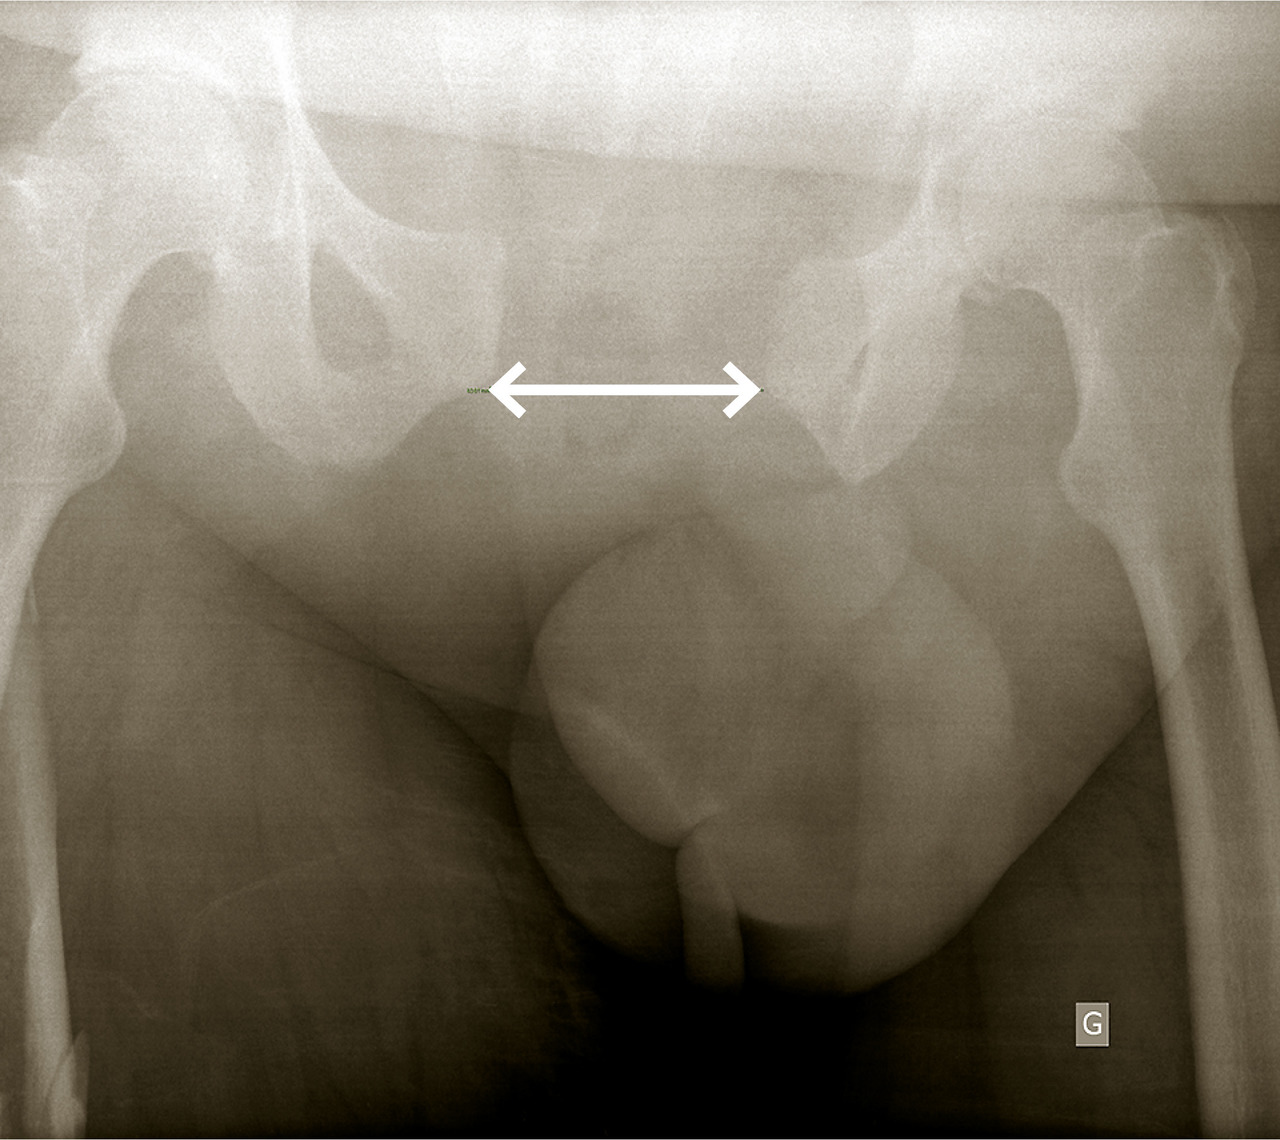

• une radiographie du bassin de face (fig. 3), à la recherche d’un fracas de l’anneau pelvien ; en l’absence d’autre cause évidente de défaillance circulatoire, elle oriente vers une hémorragie pelvienne et rétropéritonéale.

Traumatisme pelvien

Les lésions pelviennes peuvent être responsables d’hémor­ragies non diagnostiquées et fatales pouvant être d’origine artérielle, veineuse ou osseuse. L’hémostase doit être initiée dès le ramassage du blessé grâce à la pose d’une ceinture de contention pelvienne ; elle repose ensuite sur l’embolisation radiologique des saignements artériels. Un packing pelvien chirurgical et la pose d’un fixateur externe de bassin peuvent également être envisagés. Des lésions viscérales, notamment de l’appareil urinaire et anorectales, peuvent être associées.